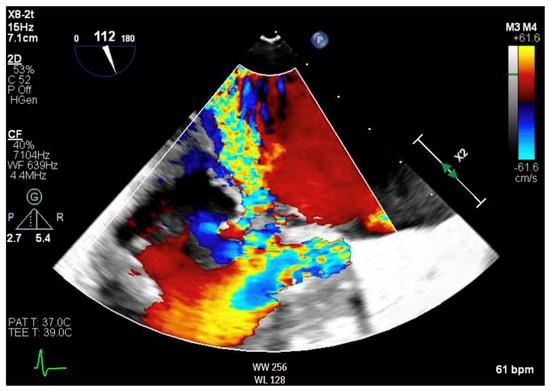

Transthoracic echocardiogram (TTE) showed severe asymmetric left ventricular hypertrophy, preserved left ventricular ejection fraction at 65–70%, systolic anterior motion (SAM) of the mitral valve (Figure 1 and Supplementary Video S1), left ventricular outflow tract (LVOT) obstruction with a peak velocity of 7.1 m/s at rest and an eccentric, posteriorly directed mitral regurgitant jet (Figure 2). Pharmacological myocardial perfusion SPECT with gated imaging was obtained one year prior to presentation and showed normal myocardial perfusion, left ventricular volume and systolic function. Cardiac magnetic resonance imaging showed left ventricular hypertrophy with a maximal thickness of 1.7 cm at the mid-ventricular septum and late gadolinium enhancement in the lateral and inferior half of the left ventricle, the basal inferolateral wall, the apical lateral walls and the apical anterior wall (Figure 3a,b). These findings were consistent with a diagnosis of HCM with outflow tract obstruction; thus, the patient was started on beta blockers.

Figure 1.

Parasternal long axis view on TTE showing left ventricular hypertrophy and SAM.

The patient had initial symptomatic improvement after the initiation of beta blockers but returned three months later with worsening dyspnea. Repeat TTE showed the resolution of SAM and LVOT obstruction, indicating that the initial SAM was related to dynamic LVOT obstruction, flow acceleration and Venturi forces related to the hyperdynamic state. However, there was persistent posterior MR despite the resolution of SAM, indicating a SAM-independent cause of primary MR that may have been missed on transthoracic imaging (Figure 4 and Figure 5, Supplementary Videos S2 and S3). Additionally, there was new right ventricular enlargement and an elevated pulmonary artery systolic pressure of 74 mmHg.

Figure 5.

Parasternal long axis view showing posteriorly directed MR.

Figure 7.

TEE demonstrating posteriorly directed MR.